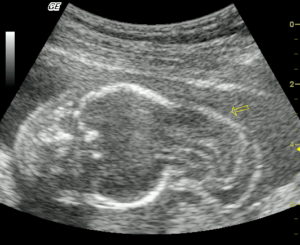

20 неделя беременности соответствует пятому акушерскому месяцу и считается половиной гестационного периода.

На этом сроке будущей маме предстоит пройти плановое ультразвуковое исследование, которое позволит:

- тщательно осмотреть провизорные (временные) органы эмбриона – хорион, желточный мешочек, амнион, плаценту;

- изучить структуры тела, конечностей и лица на предмет наличия патологий развития;

- определить пол ребенка;

- оценить состояние родовых путей.

Что покажет ультразвуковое сканирование?

Во II триместре гестации врач-сонолог проводит определение:

- предлежания плода;

- окружностей живота, грудной клетки и головы, а также ее продольный и поперечный размеры;

- длины костей;

- структур лица, головного и спинного мозга;

- состояния позвоночного столба, брюшной полости и сердечной мышцы;

- развития пищеварительного тракта и мочевыделительной системы;

- зрелости плаценты и ее расположения относительно внутреннего зева матки;

- количества амниотической жидкости;

- численности сосудов в пупочном канатике, скорость и характер кровообращения;

- мышечного тонуса матки.

Врач, выполняющий обследование, показывает будущей маме ее кроху на экране ультразвукового аппарата, для получения более точного изображения стоит записаться на трехмерное (3д) или четырехмерное (4д) УЗИ